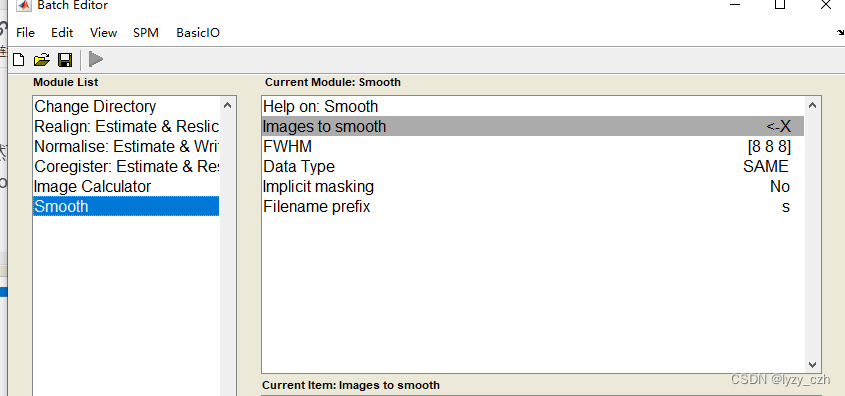

5)去头颅

点击ImCalc

弹出如下界面,Input Images先选择MRI的图像,即wmxxxx.nii(也可以选MRI模板),再选rwmeanxxxx.img,Expression输入i2.*(i1>0.05),其中i1表示第一张图像,i2表示第二张,运行后会在matlab的当前路径输出结果,我这里是PETprocess\processing,所以在下面会生成output图像。

打开output图像如下:

注意在Image Calculator的Expression输入是固定的因此可以直接在这里输入如下: